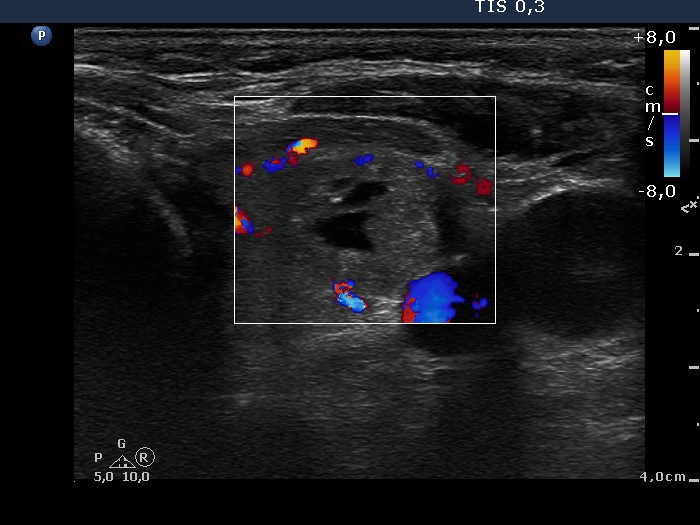

Ultrasonography. The thyroid was composed of multiple nodules with different echogenicities. There was a small hypoechogenic lesion above the right lobe.